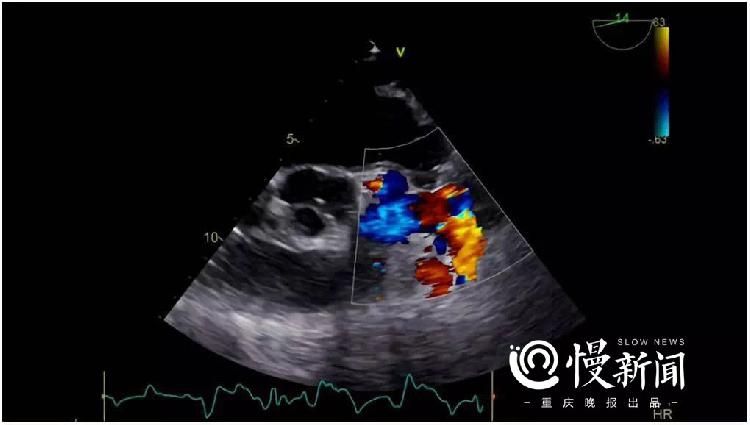

2015年,袁荣在一次结石治疗中,无意通过心脏彩超得知了自己的心脏和旁人大不相同。“简单来说,就是普通人的心脏由主动脉供血,而患者是由肺动脉供血。”刘作金主任告诉记者,“肺动脉”供的其实是一种静脉血,压力比主动脉低很多。这让心肌细胞不能得到正常的供氧,会导致心脏长期处于缺血状态。

手术有条不紊而紧张进行,术中食道心脏超声(TEE)实时监测着袁荣心脏的各项指标,并同步评估冠状动脉血流动力学和肺动脉压力。同时,根据监测数据调节肺动脉压力、降低冠脉窃血、保障心肌灌注,手术平稳顺利地完成。

4小时后,左肝切除及胆管空肠吻合术成功完成。经二维超声斑点追踪证实,患者在左冠状动脉支配区域心肌功能得到改善,在手术室就已完全清醒并拔除气管导管,并于术后第二天就从ICU送回普通病房继续观察。